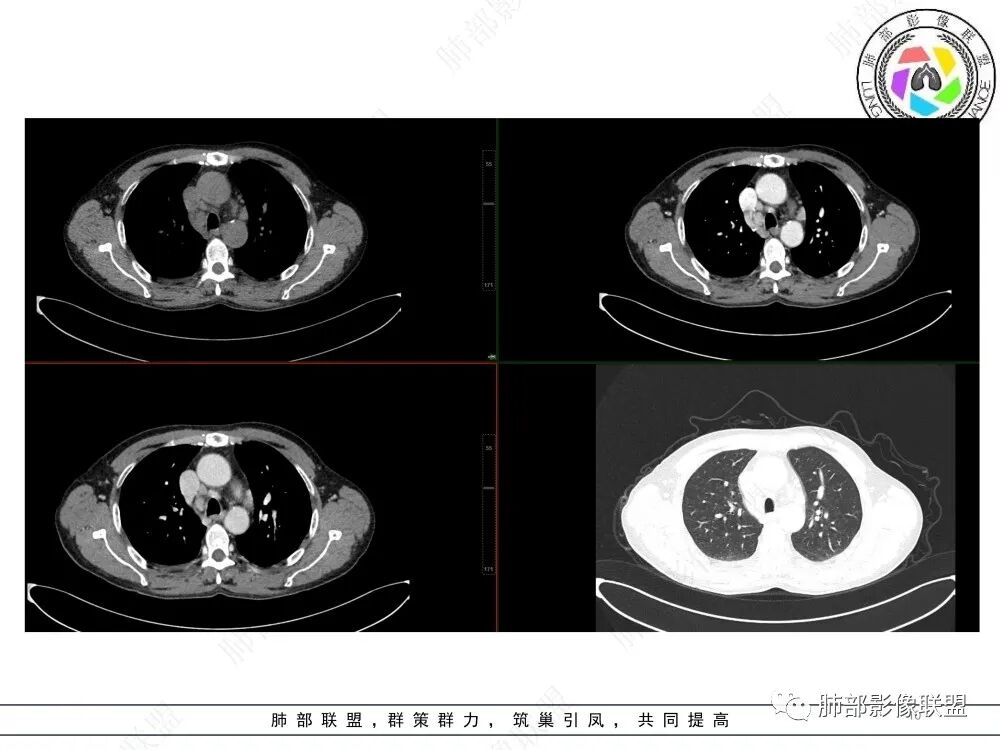

高巧灵:右肺自中间段支气管以下支气管狭窄,周围见软组织影,密度较高,并见钙化,右下肺不张,右侧胸腔少量积液。纵隔多发稍大淋巴结,密度较高,强化均匀,倾向淀粉样变性,结核其次,粘表待排。

白光宇:右下肺门不规则软组织影,包绕支气管,近端支气管狭窄阻塞,远端肺组织阻塞性不张,伴支气管粘液栓,血管显示尚可,纵膈淋巴结肿大,考虑粘液表皮样癌,鉴别结核。

刘权威: 纵隔淋巴结肿大,右肺下叶支气管狭窄,腔内似乎有丘壮突起,支气管铸型,远端阻塞性改变,右侧胸水,恶没问题,小与鳞的鉴别,不支持小的理由:小阻塞性改变发生比较晚,突破支气管周围淋巴结被摸,融合,然后侵入支气管腔内,堵塞靠肺门根部,没有冰冻改变。综合考虑鳞癌伴阻塞性改变。

袁勇: 右肺下叶支气管狭窄,管壁不规则,管腔内似可见强化的成分,结合纵隔肿大的淋巴结,考虑恶性占位。

傅昌瑜:老年男性,纵隔淋巴结肿大,支气管狭窄堵塞,考虑恶性。无冰冻肺门及冰冻纵隔,鳞癌可能性大。

鲁兆宏:右下叶支气管腔内病变及气管内粘液栓,气管环相对完整,血管走形自然,远端血管增粗。纵膈内多发淋巴结,病灶与淋巴结明显一致强化,未见明显坏死。未见明显树芽征等播散灶。考虑粘液表皮样癌或腺样囊性癌等涎腺类肿瘤。

刘悌: 右肺下叶支气管开口处见软组织密度影,相应的支气管壁较均匀增厚,支气管腔内见粘液栓,远端肺组织不张实变,增强后增厚支气管壁明显强化,考虑恶性肿瘤可能,感染性病变待排。

2.CT影像右侧中间段及右肺下叶支气管阻塞、结节影突入,局部轻度强化,未见钙化。

3.右肺下叶呈实性高密度影,体积缩小,密度较均匀,强化明显(对比胸壁肌群),肺血管走行自如,偶见含气支气管。